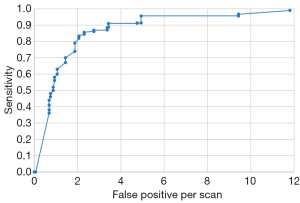

When the prediction model analyzes the input test image, it will output a value between 0 and 1, which represents the probability that the test image contains pulmonary embolism segments. By setting a threshold, we can distinguish whether the test image contains pulmonary embolism or not. At the same threshold, the ROC curves of sensitivity and false positive are shown in Figure 2. The overall sensitivity was 0.990 (99.0%). When the average number of false positives per case was 2, the sensitivity was 0.823.